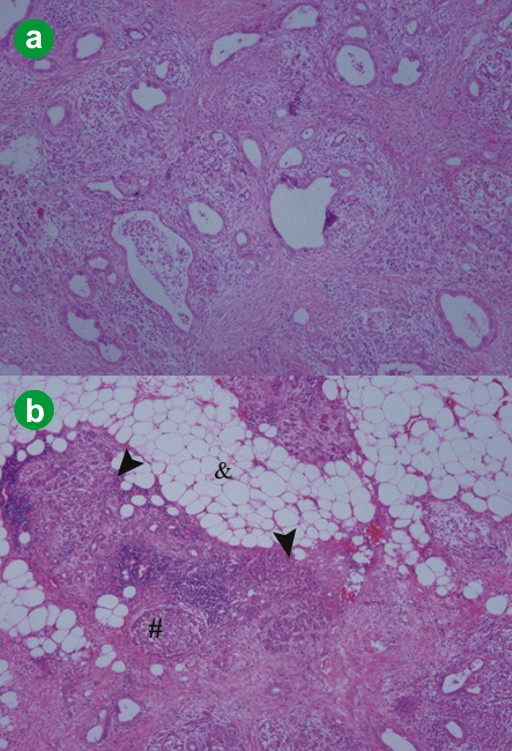

Figure 3. a. Histological features of the tumor revealed abundant fibrosis and duct lesions with various atypia (x100). b. In the periphery of the tumor, normal duct-like lesions, islets of Langerhans (#) and acinar atrophy (arrow heads) were observed and, around the tumor, abundant normal adipose tissue (&) was seen (x100). |